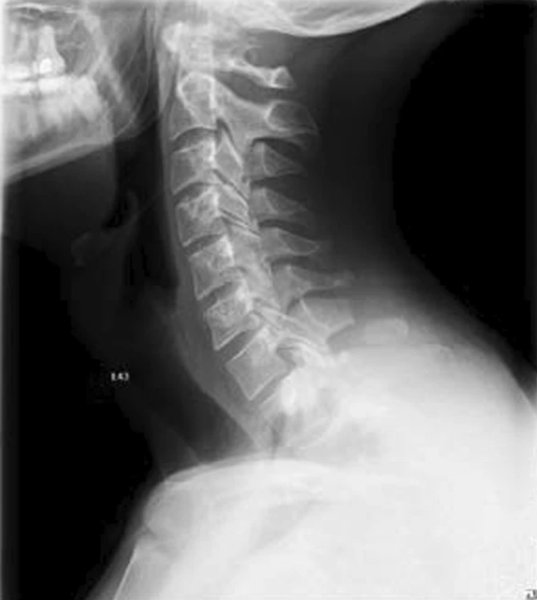

31-летний мужчина обратился в больницу при Лейпцигском университете с жалобой на острую боль и отек в области шейного отдела позвоночника. Он рассказала, что до четырех часов в день играл в VR, часто повторяя одни и те же движения руками, плечами и головой "в соответствии с ритмическими визуальными и музыкальными указаниями".

В результате седьмой шейный позвонков сильно "стерся", а его остистый отросток треснул, не выдержав нагрузок. Как подчеркивают медики, это первый в мире стрессовый перелом из-за виртуальной реальности, обычно от таких травм страдают спортсмены, военнослужащие и шахтеры. Врачи обследовали пациента при помощи магнитно-резонансной томографии и исключили дефект мягких тканей, после чего начали лечение с обезболивающими препаратами. Спустя 6 недель ношения бандажа, немец восстановился без осложнений.